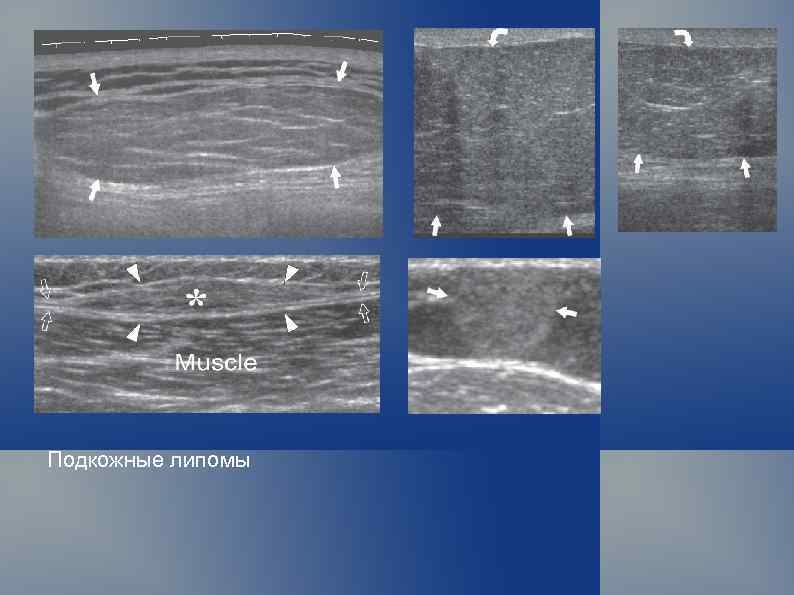

Подкожные липомы